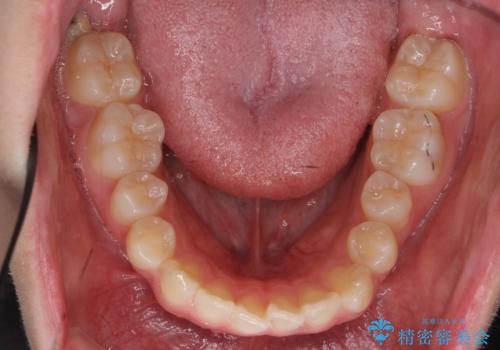

前歯のがたつき 乳歯を抜かずに矯正

- 前歯のがたつきを主訴に来院。

右上に乳歯が残っていましたが、後継永久歯がないため、抜かずに矯正しました。

乳歯の部分が反対咬合でしたが、歯列矯正で被蓋が改善するように移動させました。

右上の乳歯は移動させましたが、幸い矯正後にぐらつくこともなく、そのまま抜けるまで使うことにしました。